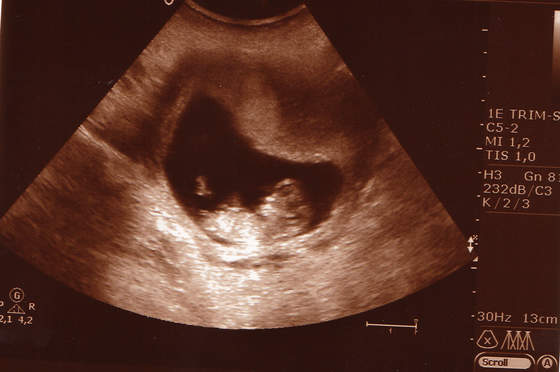

To nasze fotki z USG w poniedziałek!:-)